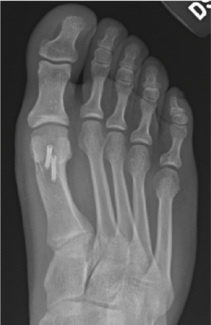

The focus for this column is 3-fold: functional hallux limitus, symptomatic hallux limitus, and traditional surgical outcomes.